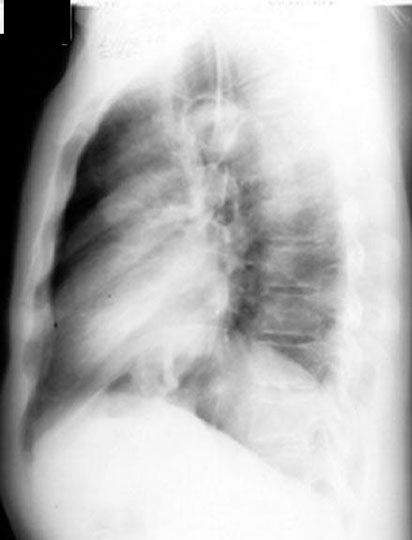

2 Thin Walled Cavities

Old Coccidioidomycosis